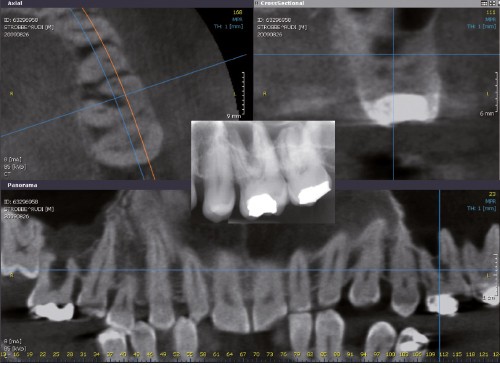

En complément de son examen clinique, afin d’explorer un site implantaire ou bien encore de confirmer une hypothèse diagnostique, le praticien peut faire appel à des examens radiologiques complémentaires qu’il ne peut réaliser au cabinet, faute d’installations appropriées ou d’autorisation de les pratiquer lui-même.

Dans le domaine maxillo-facial, l’IRM est requise essentiellement pour l’imagerie des tissus mous de l’articulation temporomandibulaire (ATM) (fig. 1).

Le praticien, dans son courrier adressé au radiologue, précisera le contexte clinique et, d’une manière la plus détaillée possible, les images qu’il souhaite obtenir : images bouche ouverte, bouche fermée par exemple, résolution, séquences, champs examinés…